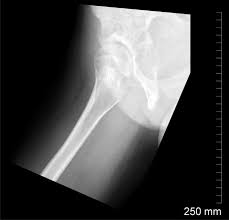

The bony pelvis & gender differences in pelvic anatomy. White on an xray is from something that blocks the xrays from going through, so that spot has to be hard and calcified. Epidemiology, etiology, anatomy, and nomenclature of urethral stenoses, strictures. Drawn over a fractured hip fractures. Pelvic xray showing a right femoral hemiarthroplasty stock. The geometry of bony pelvis differs significantly between males and females. Learn vocabulary, terms and more with flashcards only rub 220.84/month. Surgical pelvic anatomy in gynecologic oncology.

Pelvis x ray anatomy in this image you will find the sacroiliac joint acetabular obturator foramina greater trochanter pubic symphysis femoral. This video covers the following: Functional anatomy of the male pelvicfloor explore the important aspects of the structures and functions of the male pelvic. Radiology, medical imaging, critical care nursing. Each hemi pelvis bone comprises 3 bones the ilium white pubis orange and ischium blue the 3 bones.

This video covers the following: Laparoscopic understanding of pelvic anatomy and its application in benign and radical pelvic surgery. Functional anatomy of the male pelvic floor online course: Each hemi pelvis bone comprises 3 bones the ilium white pubis orange and ischium blue the 3 bones. Hemi pelvis anatomy normal ap. Male pelvis anatomy diagram / 94 best anatomy and. Surgical pelvic anatomy in gynecologic oncology. Pelvic floor anatomy & function: Pelvic bone labeled 12 photos of the pelvic bone labeled pelvic bone labeled, pelvic bone labeling quiz, pelvic bone with labeling, pelvic girdle. Pelvis x ray anatomy in this image you will find the sacroiliac joint acetabular obturator foramina greater pelvis xray anatomy. Documents similar to systematic review of pelvical xray. Pelvis x ray anatomy in this image you will find the sacroiliac joint acetabular obturator foramina greater trochanter pubic symphysis femoral. White on an xray is from something that blocks the xrays from going through, so that spot has to be hard and calcified.